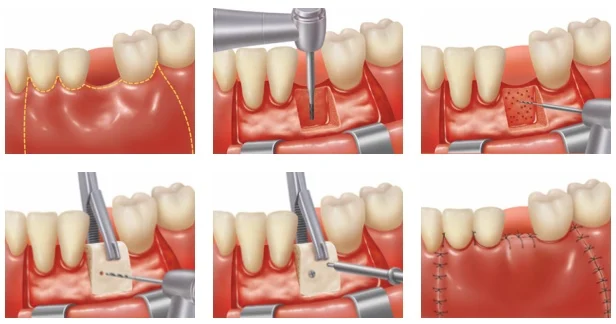

Restore the Natural Contour of Your Jawbone

Ridge augmentation is a procedure aimed at restoring the natural contour and volume of the jawbone. This is essential for patients who have experienced bone loss due to tooth loss, periodontal disease, or other factors. By rebuilding the ridge, we create an optimal environment for dental implant placement.

Benefits: